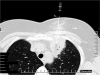

We report a 52-year-old patient who developed B-cell non-Hodgkin's lymphoma subsequent to sarcoidosis. Sarcoidosis was diagnosed 16 years ago and remained asymptomatic for 14 years after steroid treatment. She presented with new symptoms of arthralgia, photosensitivity, butterfly erythema, autoimmune antibodies (ANA, chromatin positivity) associated with progression of the known left upper lobe lesion on the chest X-ray suggesting primary autoimmune disease (systemic lupus erythematosus). As steroid treatment was not effective, we started bolus cyclophosphamide therapy after which progression was seen on the chest X-ray. Computed tomography (CT)-guided needle biopsy confirmed malignancy of indefinable origin. Despite of the well-known fluorodeoxyglucose (FDG) avidity in active sarcoidosis, a FDG-positron emission tomography (PET) scan was performed to stage the primary tumour. Intensive FDG uptake was detected in the affected lung segment, with moderate uptake in mediastinal lymph nodes. The patient underwent left upper lobectomy. The histology showed pulmonary mucosa-associated lymphoma (bronchus-associated lymphoid tissue (BALT) lymphoma) in the lung tissue, while only sarcoidosis was present in the mediastinal lymph nodes. Bone marrow biopsy was negative.The association between sarcoidosis and lymphoma is known as sarcoidosis lymphoma syndrome, which is a rare disease. PET-CT was helpful in the differentiation of sarcoidosis and malignancy in this patient. It is important to be aware of the risk of lymphoma in sarcoidosis and FDG-PET, used for adequate purpose, can help the diagnosis.